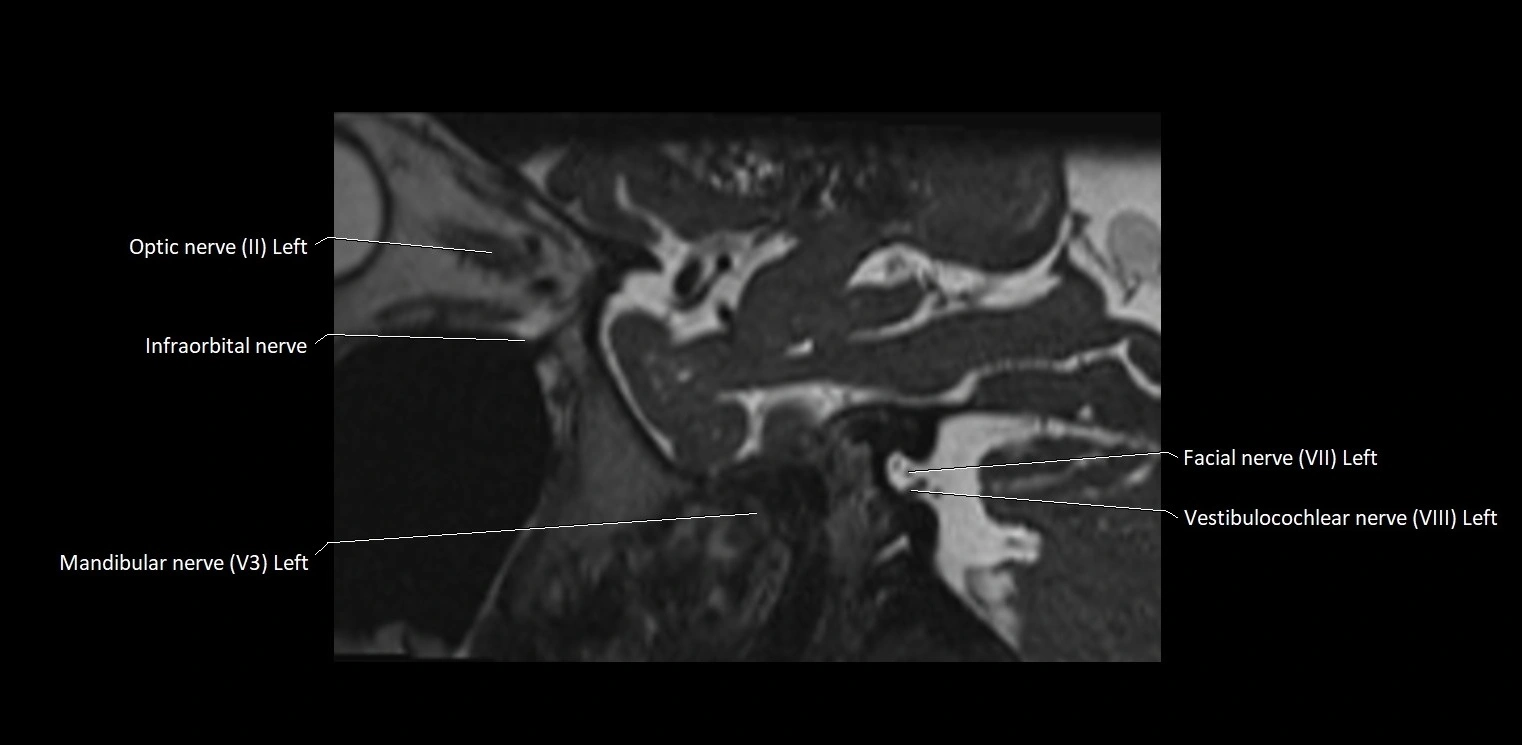

MRI Appearance

• The abducens nerve is a small, thin, linear structure

• Best visualized on high-resolution T2-weighted 3D MRI sequences (e.g., FIESTA or CISS)

• Seen as a hypointense (dark) line running from the brainstem at the pontomedullary junction, traversing the prepontine cistern, and entering Dorello’s canal under the petrosphenoidal ligament, then into the cavernous sinus, and finally the orbit

• May be challenging to visualize in standard MRI due to its small size

• Pathology may be inferred by absence, displacement, or enhancement of the nerve

MRI images

image